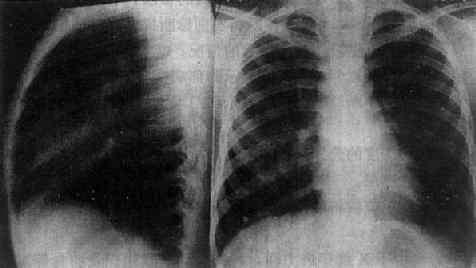

(1)一侧性肺不张:X线现为患侧肺野均匀致密,纵隔向患侧移位,肋间隙变窄(图3-1-7)。健侧肺可有代偿性肺气肿。

图3-1-7 一侧性肺不张

左侧支气管阻塞引起左侧全肺不张,显示左侧肺野均匀致密,

纵隔向患侧移位,肋间隙变窄,膈升高